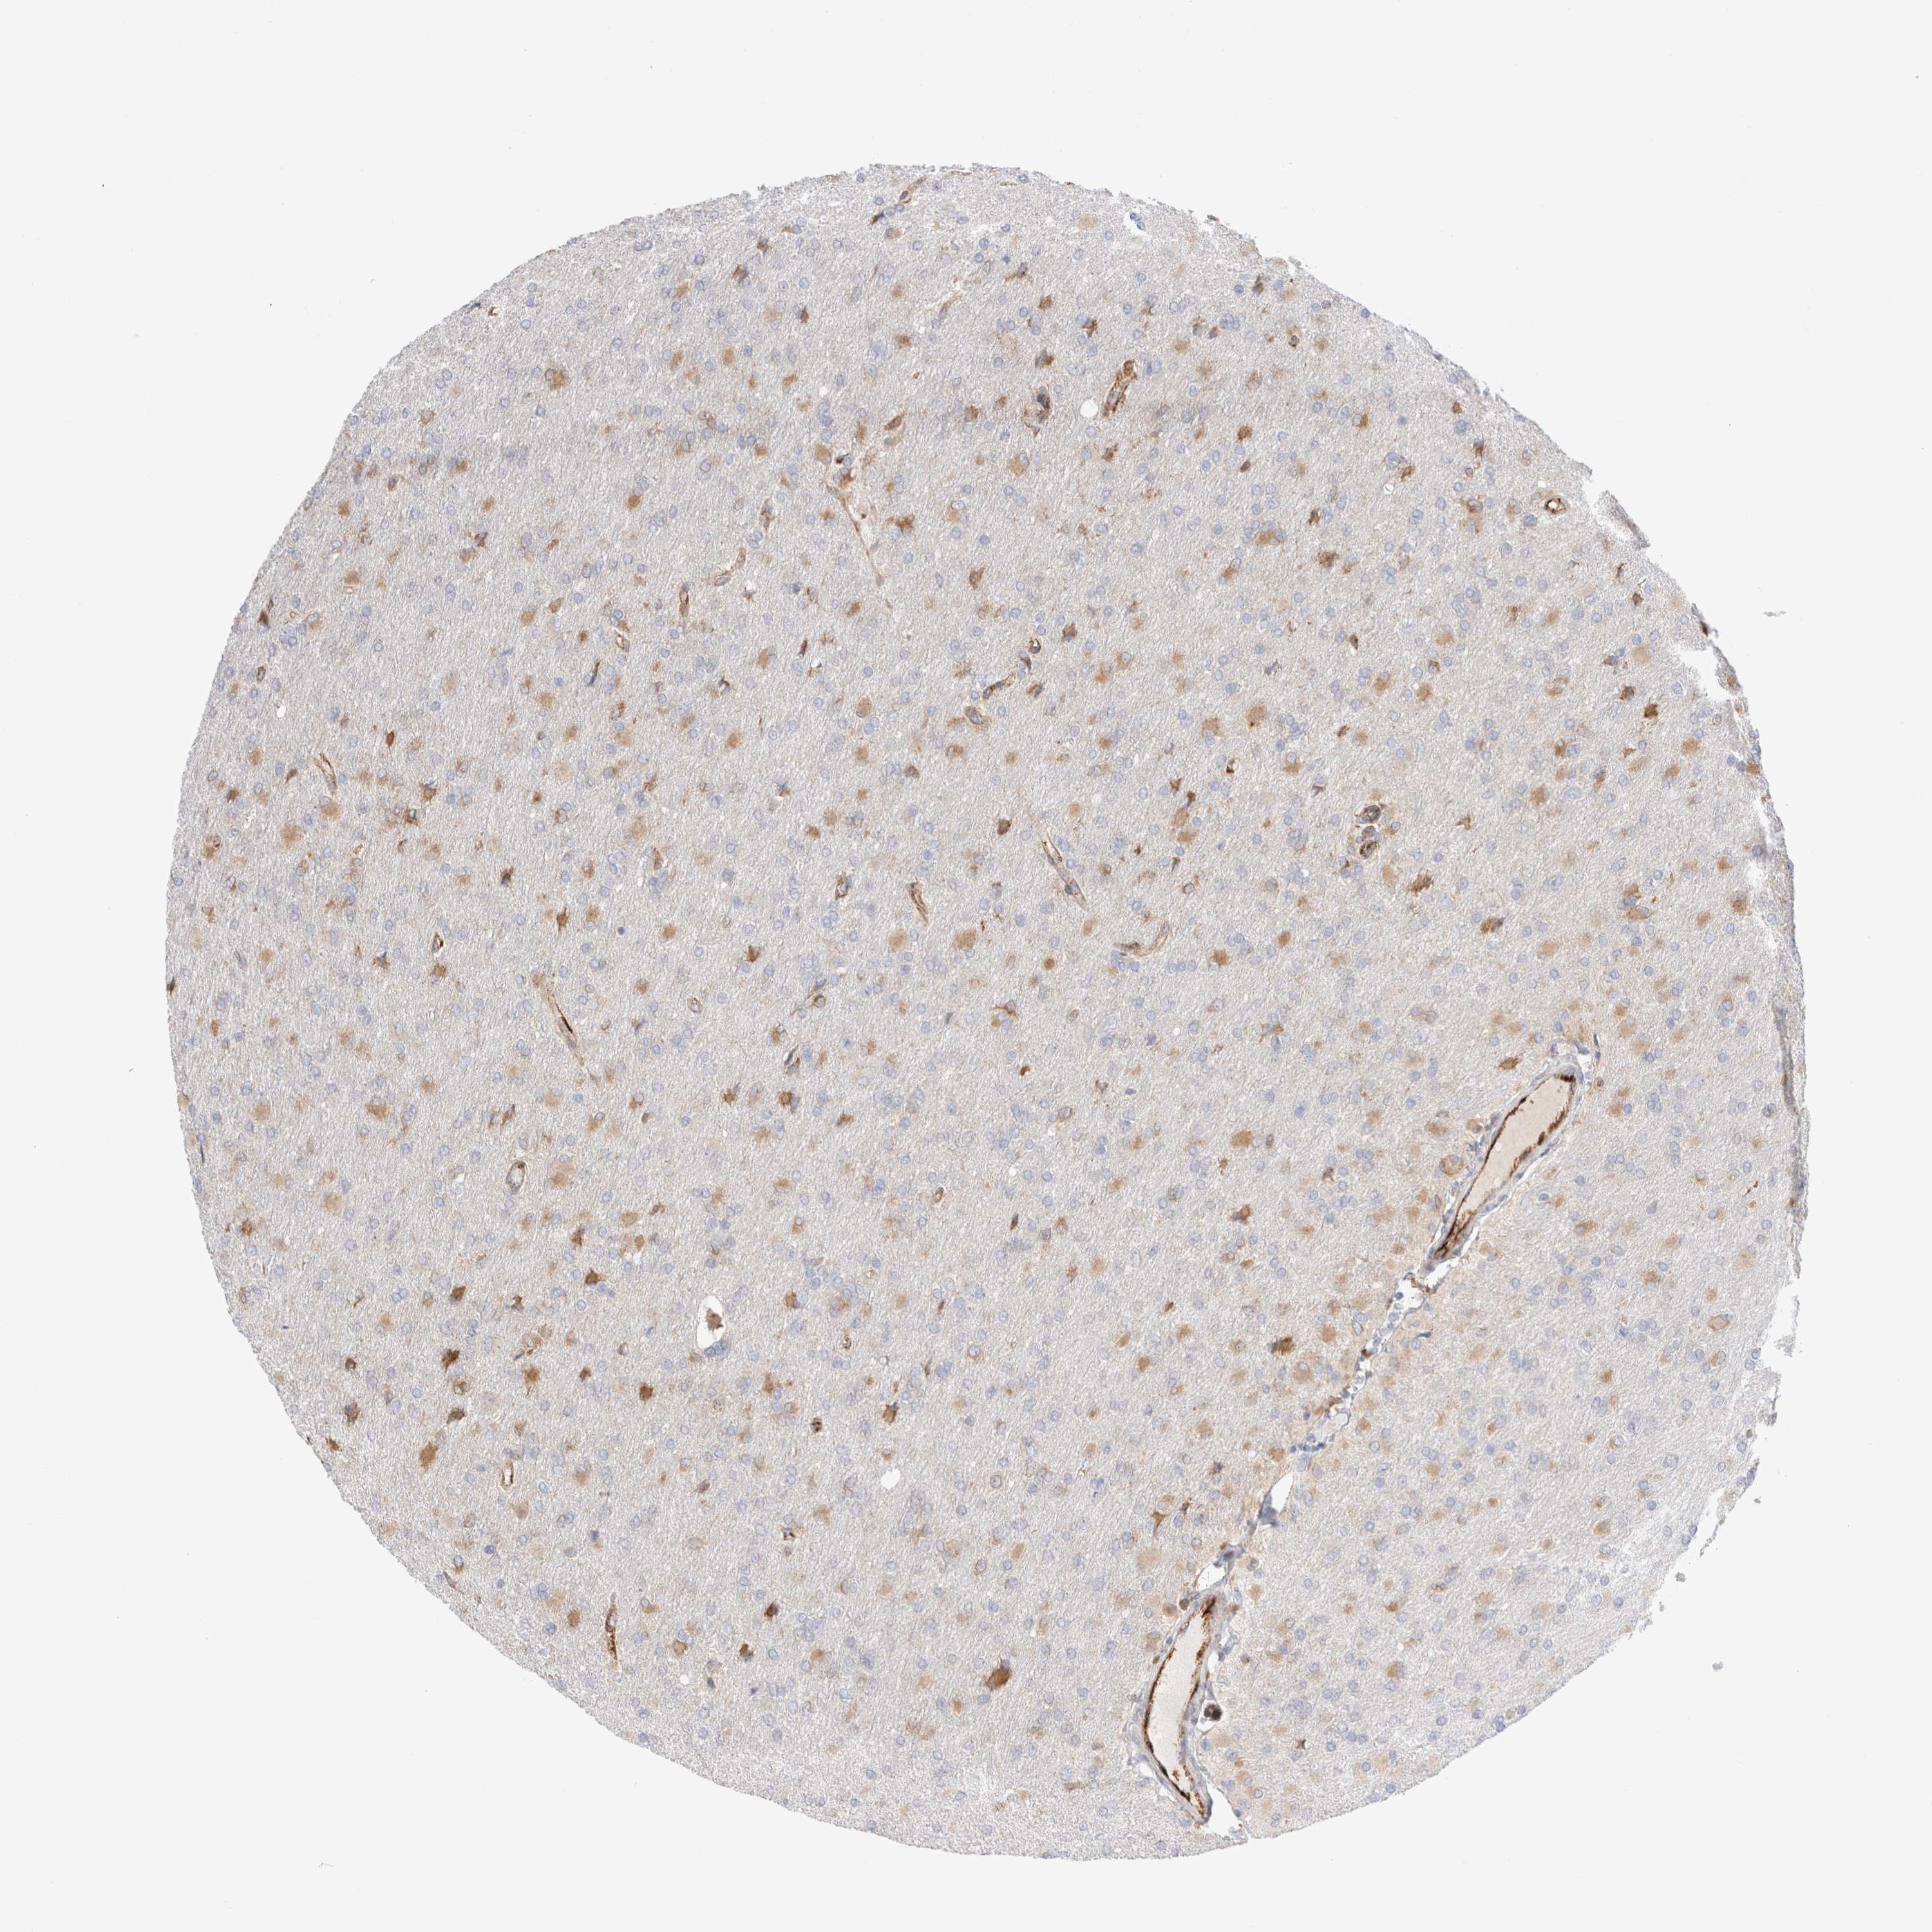

GLIOMA - Protein expressioni

A mouse-over function shows sample information and annotation data. Click on an image to view it in a full screen mode. Samples can be filtered based on level of antibody staining by selecting one or several of the following categories: high, medium, low and not detected. The assay and annotation is described here.

Note that samples used for immunohistochemistry by the Human Protein Atlas do not correspond to samples in the TCGA dataset.

Antibody stainingi

Antibody staining in the annotated cell types in the current human tissue is reported as not detected, low, medium, or high, based on conventional immunohistochemistry profiling in selected tissues. This score is based on the combination of the staining intensity and fraction of stained cells.

Each image is clickable and will lead to virtual microscopy that enables deeper exploration of all samples and also displays staining intensity scores, fraction scores and subcellular localization as well as patient and tissue information for each sample.

Antibody HPA014166

Antibody HPA025240

Staining

High

Medium

Low

Not detected

Intensity

Strong

Moderate

Weak

Negative

Quantity

>75%

75%-25%

<25%

None

Location

Nuclear

Cytoplasmic/membranous

Cytoplasmic/membranous,nuclear

Glioma, malignant, High grade

Glioma, malignant, Low grade